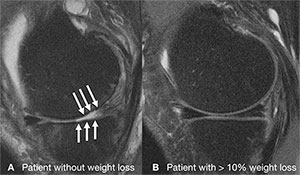

Dr. Gersing and colleagues recently investigated the association between different degrees of weight loss and the progression of knee cartilage degeneration in 506 overweight and obese patients from the Osteoarthritis Initiative, a nationwide research study focused on the prevention and treatment of knee osteoarthritis. The patients either had mild to moderate osteoarthritis or risk factors for the disease. They were divided into three groups: a control group who did not lose weight, a second group who lost a little weight, and a third group who lost more than 10 percent of their body weight. The researchers then used MRI to quantify knee osteoarthritis.

"Through T2 relaxation time measurements from MRI, we can see changes in cartilage quality at a very early stage, even before it breaks down," Dr. Gersing said.

When the researchers analyzed differences in the quality of cartilage among the three groups over a four-year time span, they found evidence that weight loss has a protective effect against cartilage degeneration and that a larger amount of weight loss is more beneficial.

"Cartilage degenerated a lot slower in the group that lost more than 10 percent of their body weight, especially in the weight-bearing regions of the knee," Dr. Gersing said. "However, those with 5 to 10 percent weight loss had almost no difference in cartilage degeneration compared to those who didn't lose weight."